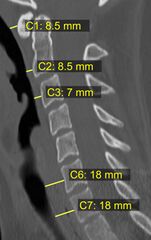

في حالات الصدمات، يعتبر زيادة سمك الحيز الفقري الأمامي علامة على الإصابة، ويمكن قياسه باستخدام التصوير الطبي.[4]

On plain radiography, prevertebral space should be less than 6 mm at C3 vertebral level in children; while in adults, the space should be less than 6 mm at C2 level and less than 22 mm at C6 level. Causes of enlarged prevertebral space could be edema, hematoma, abscess, tumors, and post surgical changes.[5]